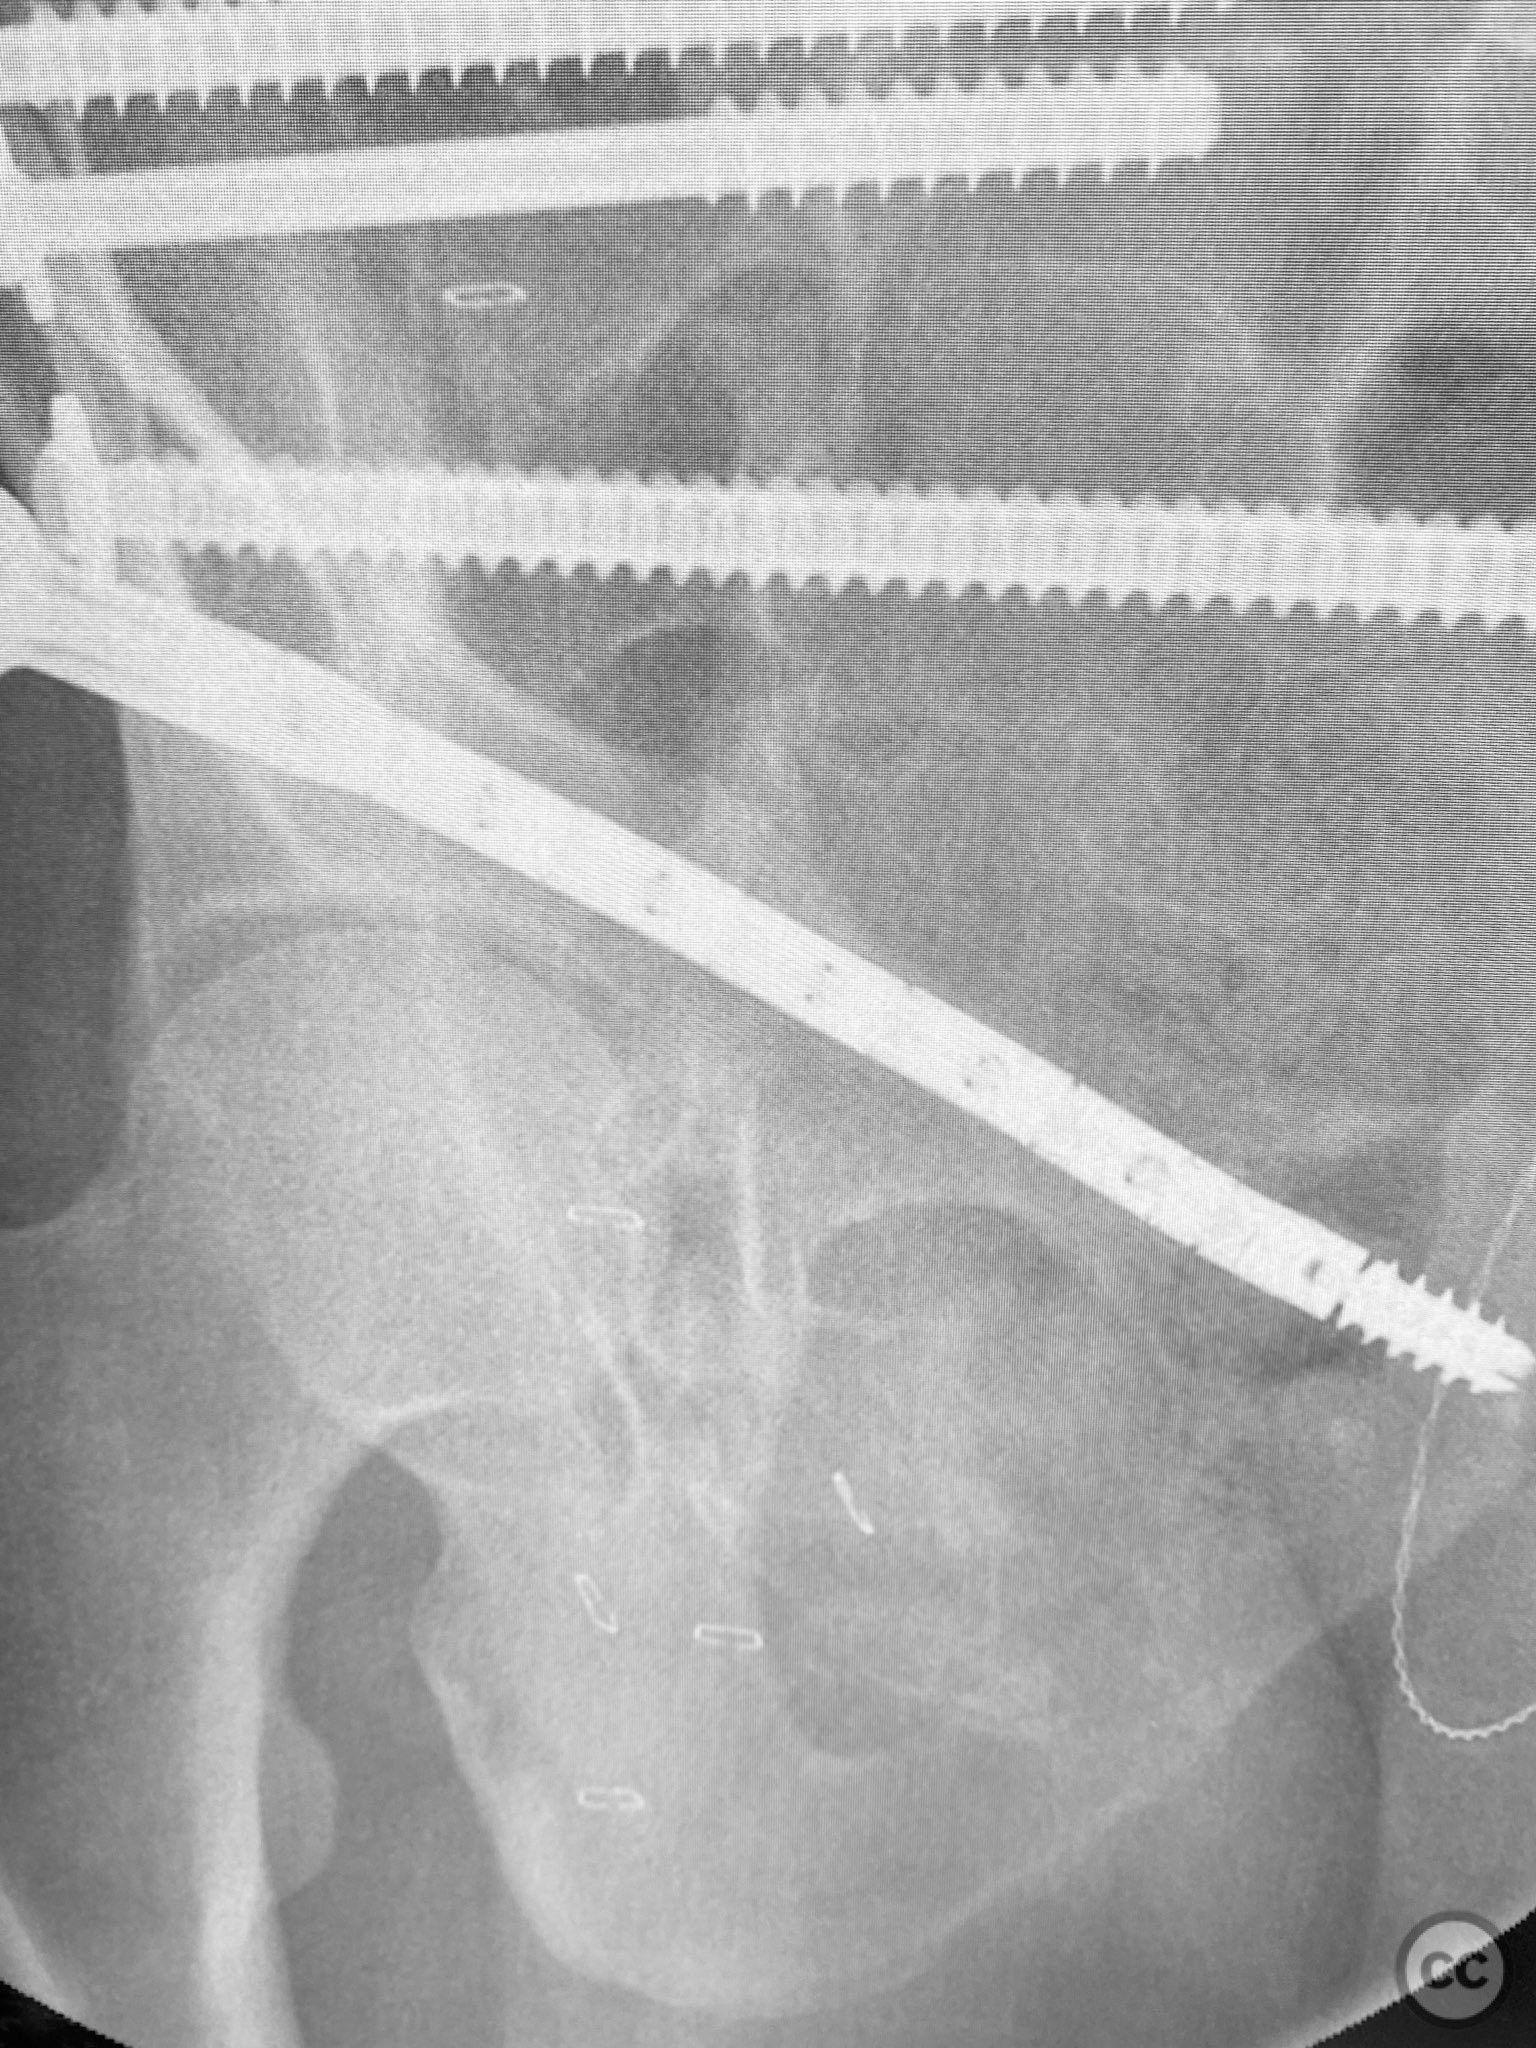

Clinical and radiological findings:  A patient sustained a high-energy lap belt injury resulting in an H-pattern sacral fracture (AO/OTA 61-C1.3) and bilateral pubic ramus fractures (AO/OTA 61-C1.3). Initial clinical assessment revealed a hemodynamically stable patient with no neurological deficit. Radiological evaluation with pelvic radiographs and computed tomography demonstrated a complete H-type sacral fracture involving both sacral ala and the central sacral body, as well as displaced bilateral superior and inferior pubic ramus fractures. No associated acetabular or hip dislocation was identified.

Planning remarks:  The preoperative plan was to achieve stabilization of the bilateral pubic ramus fractures using a 7.5mm CurvaFix medullary device, selected for its ability to conform to the curved osseous pathway of the pubic ramus. Percutaneous fixation of the sacral fracture was planned using standard iliosacral screw technique.

Anatomical surgical approach:  A percutaneous approach was utilized for the pubic ramus fixation. A small stab incision was made over the anterior aspect of the pubic tubercle. Blunt dissection was carried down to bone, and a guidewire was advanced under fluoroscopic guidance along the intramedullary canal of the superior pubic ramus, traversing the fracture site. The 7.5mm CurvaFix medullary device was then inserted over the guidewire, conforming to the osseous curvature and achieving stable fixation across the fracture. The procedure was repeated for the contralateral side. For sacral fixation, percutaneous iliosacral screws were placed under fluoroscopic guidance through small lateral incisions over the posterior ilium.

The use of the CurvaFix medullary device allowed for anatomic alignment and stable fixation of the bilateral pubic ramus fractures by accommodating the natural curvature of the osseous pathway, which is often challenging with traditional straight implants. This technique provided robust fixation in a fracture pattern that is historically difficult to stabilize, minimizing soft tissue disruption and facilitating early mobilization.

Orthopaedic implants used:   7.5mm CurvaFix Medullary Device (bilateral). Cannulated iliosacral screws.